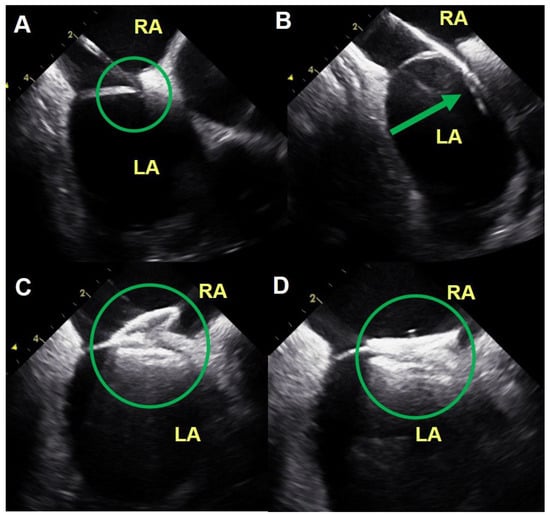

2.4. ICE Guided PFO Closure Procedure

2.5. Postprocedural Management and Study Endpoint